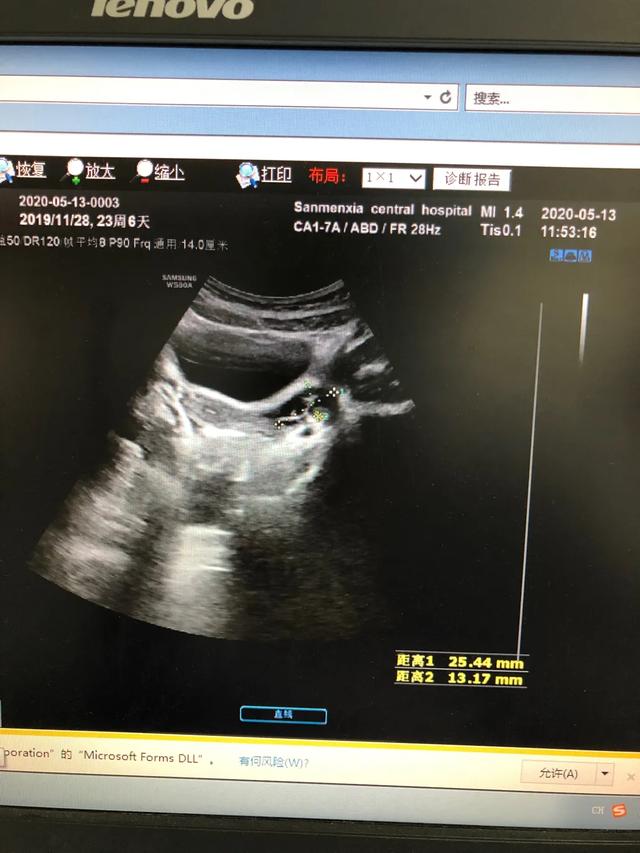

下图是一例患儿性早熟的B超结果、胸片结果及血清学化验结果。

从检查结果来看,B超显示子宫卵巢有囊性回声;胸片显示乳腺发育;而血清学指标,促黄体生成素的峰值是13.09,促卵泡的峰值是20.91,LH/FSH=62.60%。